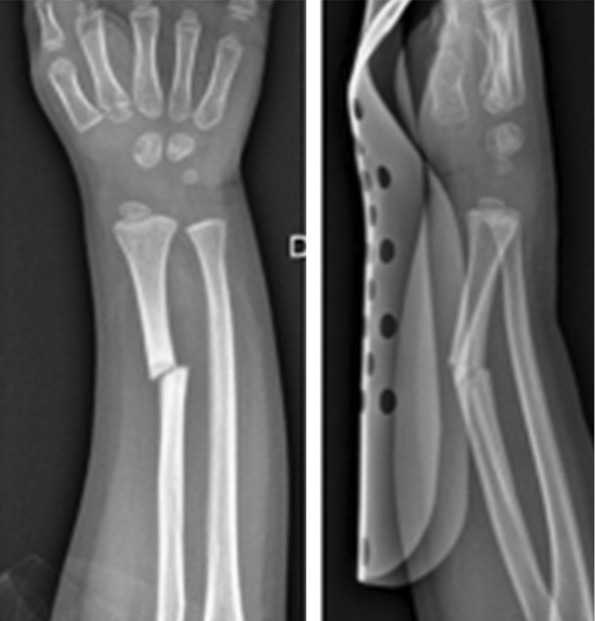

Клинически, как и по данным рентгенологического исследования, у пациента наблюдалось местное улучшение. Спустя 6 мес. после последней трансплантации спица Киршнера была удалена. При контрольном осмотре через 28 мес. у пациента зарегистрированы полная консолидация начального участка несращения, отсутствие нейроваскулярной недостаточности и суставной недостаточности. Больного можно считать выздоровевшим (рис. 7, 8).

Рис. 7. Рентгенограмма после удаления спицы Киршнера через 28 мес. после травмы